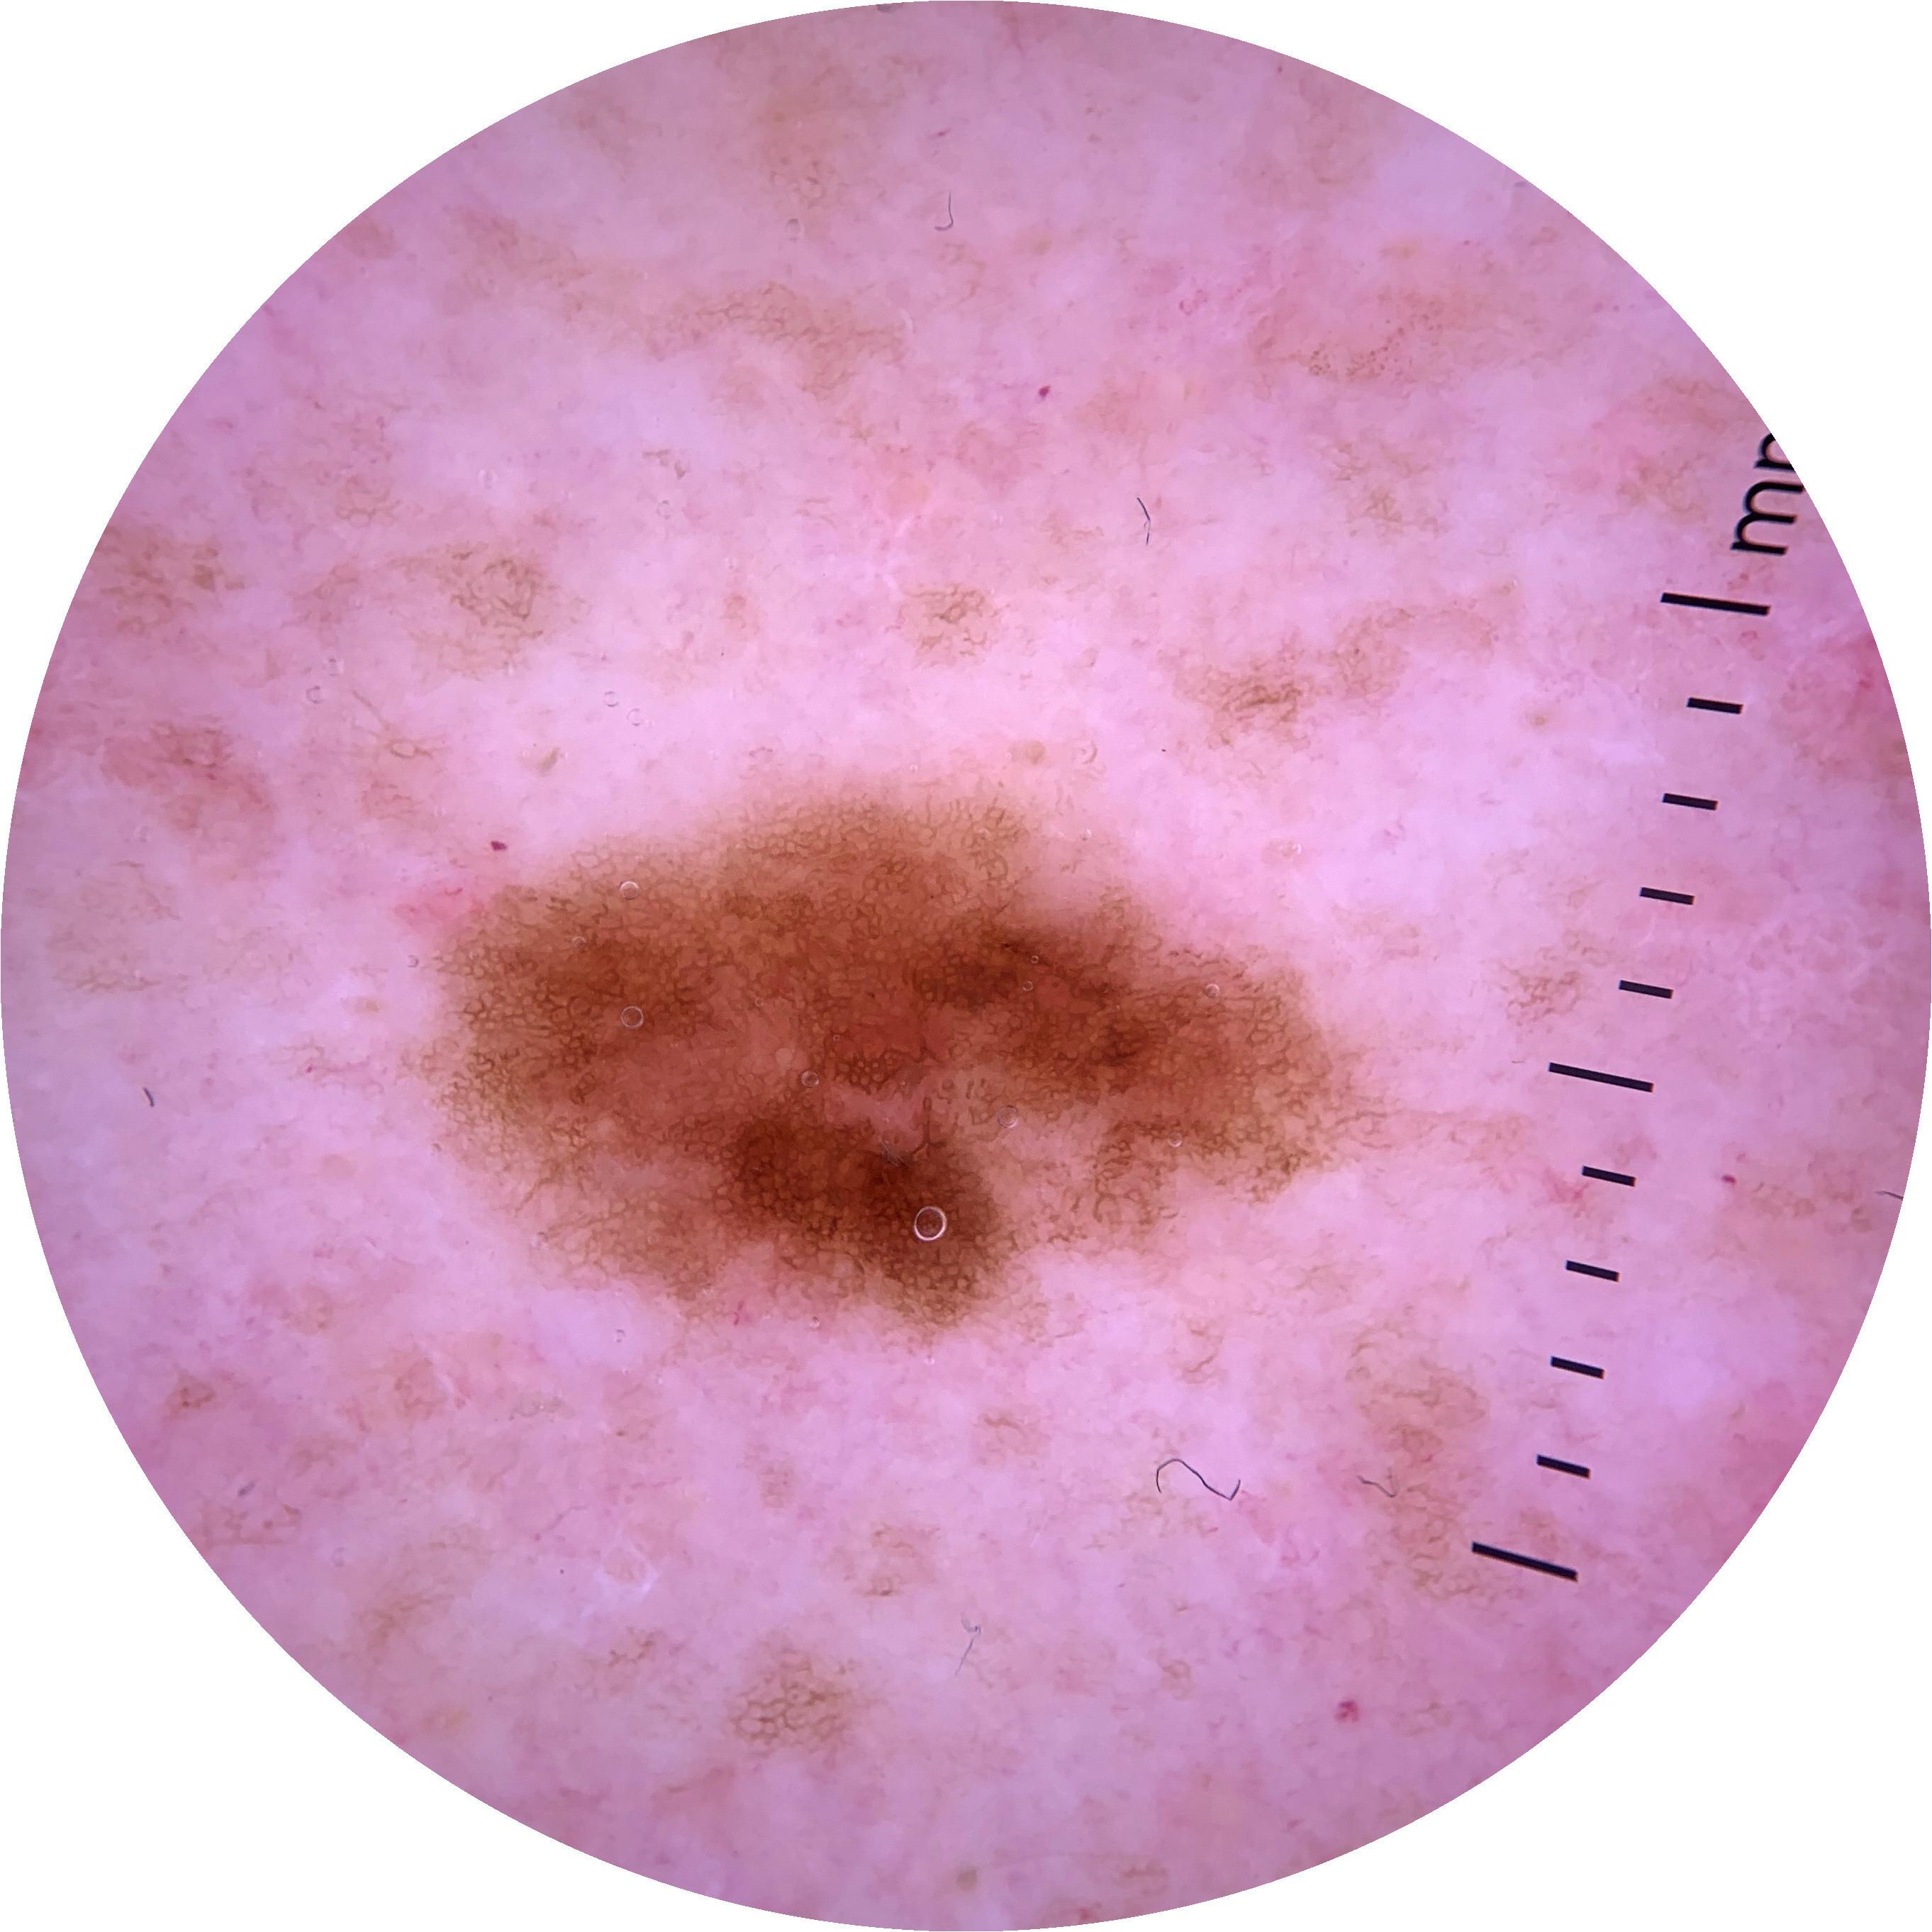

ISIC_4541529

3024 x 3024

acquisition_day 371

age_approx 70

anatom_site_1 Trunk

anatom_site_2 Posterior trunk

anatom_site_general posterior torso

diagnosis_1 Benign

diagnosis_confirm_type single image expert consensus

image_type dermoscopic